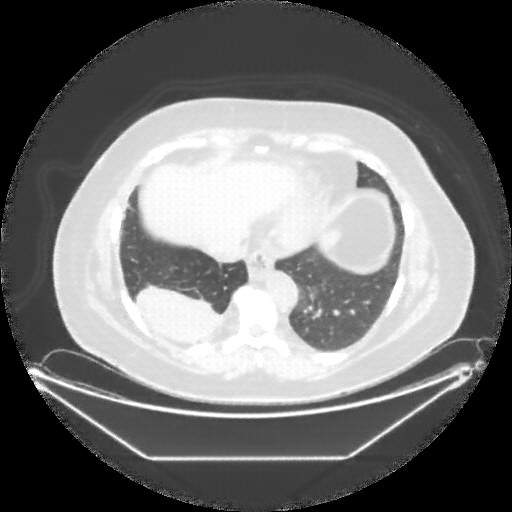

Image Grid

4Γ—3 grid: Rows show different image types (Original NATIVE, Reconstructed NATIVE, Original VENOUS, Generated VENOUS), Columns show windowing techniques (No Window, Lung Window, Mediastinum Window)

Mediastinum window (WL 40, WW 400 β†’ Low βˆ’160, High +240)

Generated VENOUS CT scan (A→B translation)

Windowing Parameters